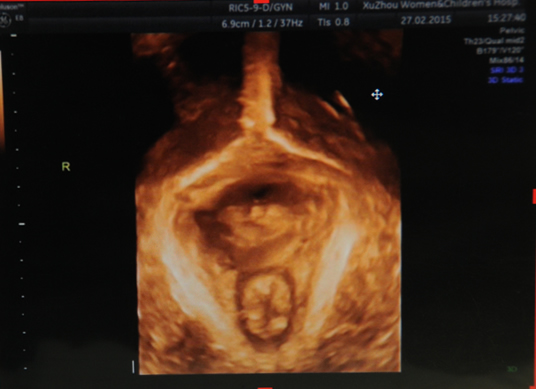

盆底三維斷層圖

盆底三維圖